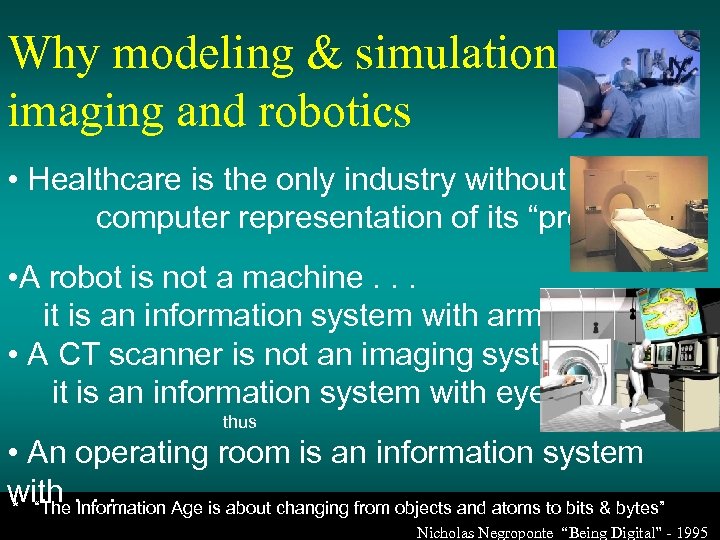

Why modeling & simulation, imaging and robotics • Healthcare is the only industry without a computer representation of its “product” • A robot is not a machine. . . it is an information system with arms. . . • A CT scanner is not an imaging system it is an information system with eyes. . . thus • An operating room is an information system with. . . * “The Information Age is about changing from objects and atoms to bits & bytes” Nicholas Negroponte “Being Digital” - 1995

Why modeling & simulation, imaging and robotics • Healthcare is the only industry without a computer representation of its “product” • A robot is not a machine. . . it is an information system with arms. . . • A CT scanner is not an imaging system it is an information system with eyes. . . thus • An operating room is an information system with. . . * “The Information Age is about changing from objects and atoms to bits & bytes” Nicholas Negroponte “Being Digital” - 1995